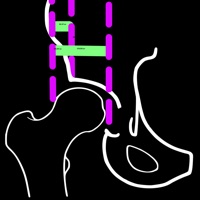

4. The migration percentage (MP) as described by Reimers is the gold standard method for assessing radiographs especially in children with hip dysplasia which quatitively shows how much femoral head has been dislocated from the ossified acetabular roof.

5. The Reimer index is calculated as the ratio (alb) x100% where a is the distance measured the lateral border of the femoral head to the Ombredanne-Perkins line and b is the width of the femoral head parallel to Hilgenreiner's line.

8. The advantage of this index is its independence of pelvic or thigh rotation and provides a good quantitative estimate of the degree of uncoverage of the femoral head.